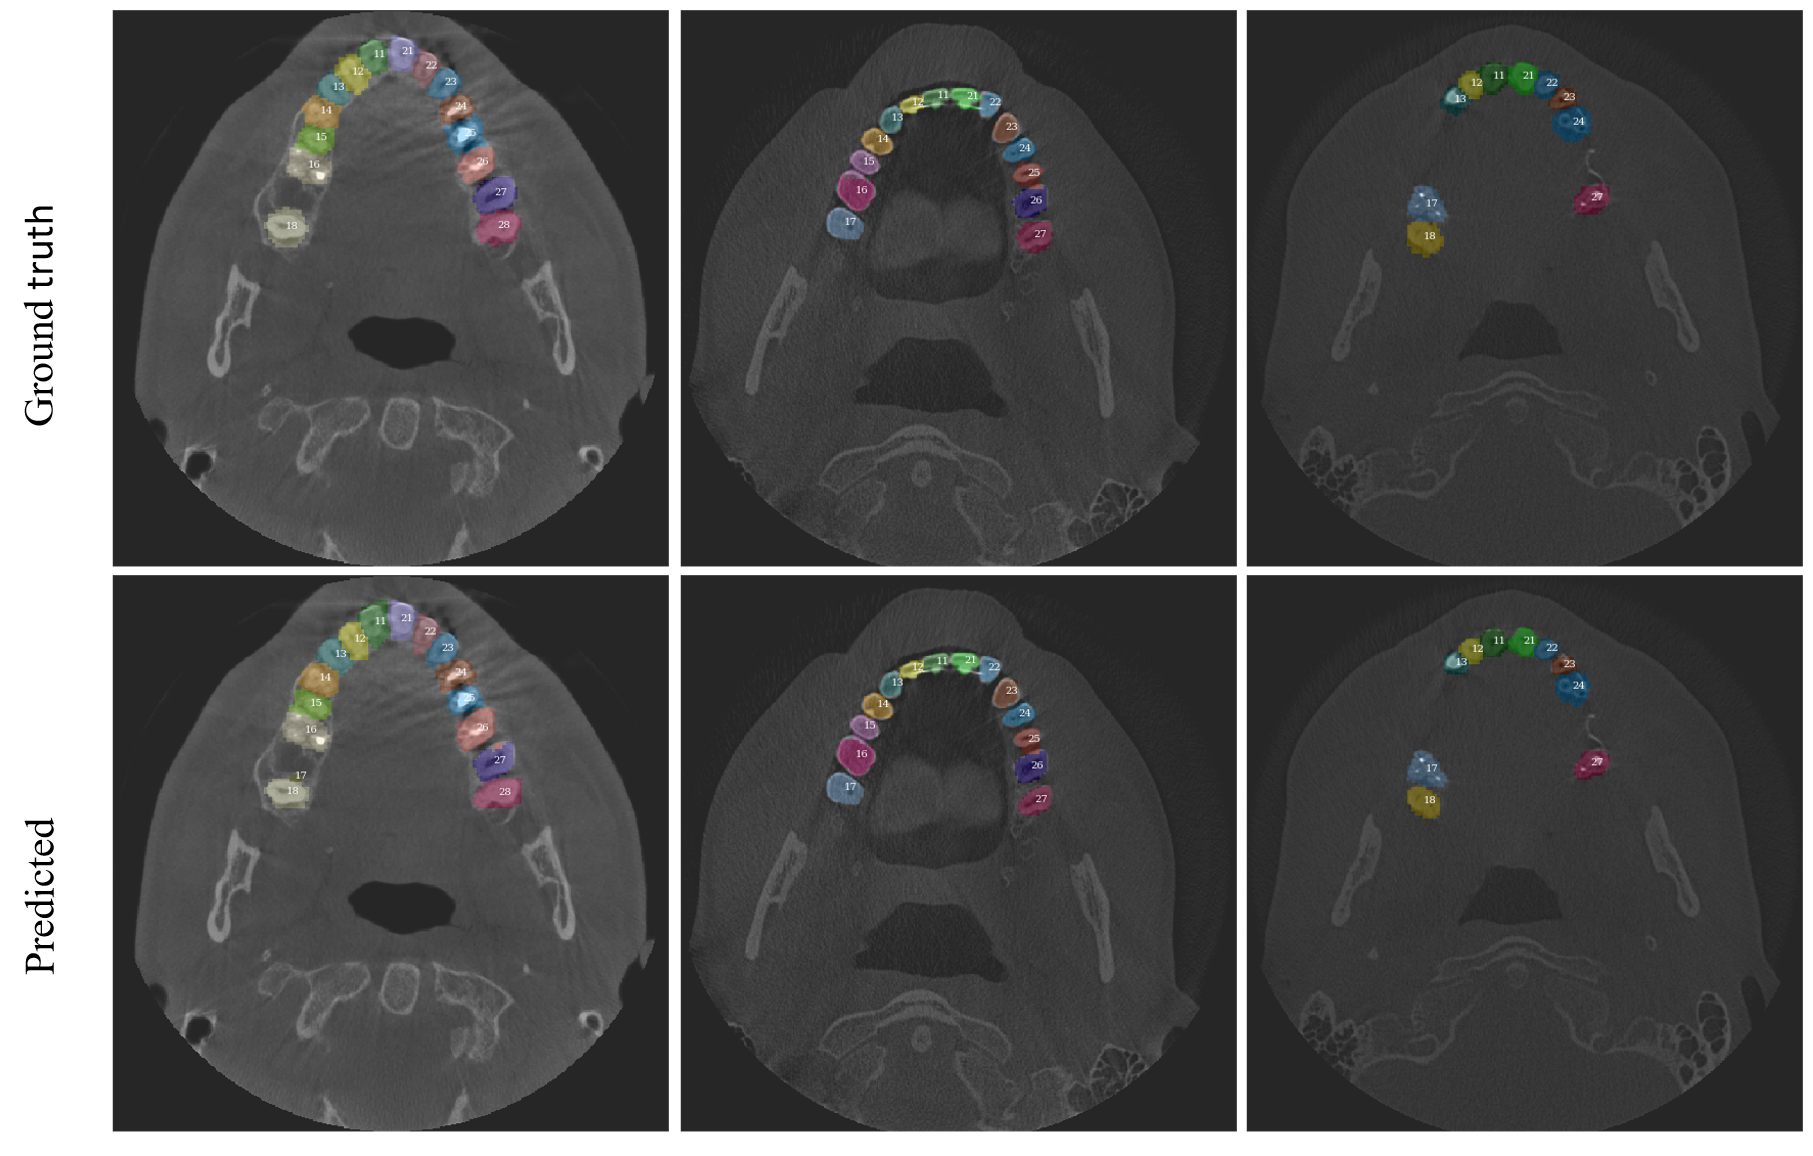

Refer to caption

Figure 4: Examples of ground truth and predicted masks. Axial slices of original CBCT scans.

Results

The localization model is able to achieve a loss value of 0.280.280.28 on a test set. The background class loss is 0.00270.00270.0027, which means the model is a capable 222-way "tooth / not a tooth" segmentor.

We also define the localization intersection over union (IoU) between the tooth’s ground truth volumetric bounding box and the model-predicted bounding box. In the case where a tooth is missing from ground truth and the model predicted any positive voxels (i.e. the ground truth bounding box is not defined), localization IoU is set to 00. In the case where a tooth is missing from ground truth and the model did not predict any positive voxels for it, localization IoU is set to 111.

For a human-interpretable metric, we use tooth localization accuracy which is a percent of teeth that have a localization IoU greater than 0.30.30.3 by our definition. The relatively low threshold value of 0.30.30.3 was decided from the manual observation that even low localization IoU values are enough to approximately localize teeth for the downstream processing. The localization model achieved a value of 0.9630.9630.963 IoU metric on the test set, which, on average, equates to the incorrect localization of 111 of 323232 teeth. Figure 4 shows examples of teeth segmentation at axial slices of 3D tensor.